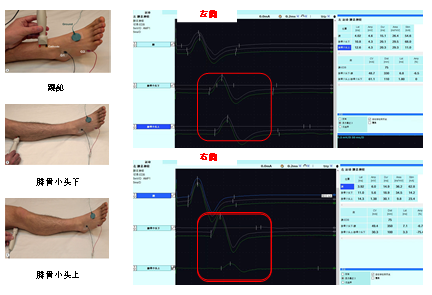

小龙今天早上起床下地时,突然摔倒在地,他发现自己的右腿麻木、无力、无法行走,经门诊医生初步诊疗,推荐他到肌电图室检查明确诊断。肌电图医师对小龙进行了简单的问诊和查体后发现,小龙主要症状为右侧足背下垂、小腿外侧到足背麻木。明确小龙的症状和体征后,根据他的情况制定相对应的肌电图检查。最后,结合小龙的症状、体征(图1)和典型的右侧腓总神经在腓骨小头处出现卡压性损害的电生理改变检查结果(图2),我们明确小龙为右侧腓总神经腓骨小头处损伤。

图2. 小龙下肢腓总神经的神经传导检测结果. 左列:腓总神经运动传导示意图;右图上:左侧腓总神经运动神经传导结果;右图下:右侧腓总神经运动神经传导结果。